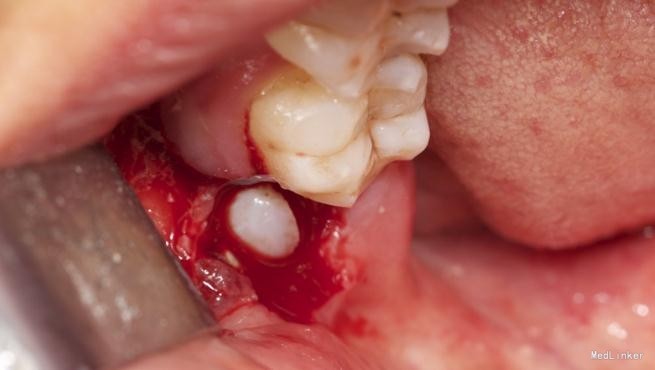

左下8水平阻生拔除

患者,男,25岁,要求拔除左下颌水平阻生牙齿,平素体质一般,无药物、食物过敏史,无高血压、心脏病等系统病史

拔除术